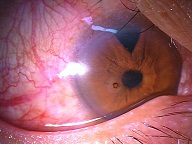

?黄斑円孔で、赤の部分の網膜が硝子体に引っ張られて断裂し、無くなってしまうと、視野の中心部が欠損、見たい部分が見えなくなってしまいます。